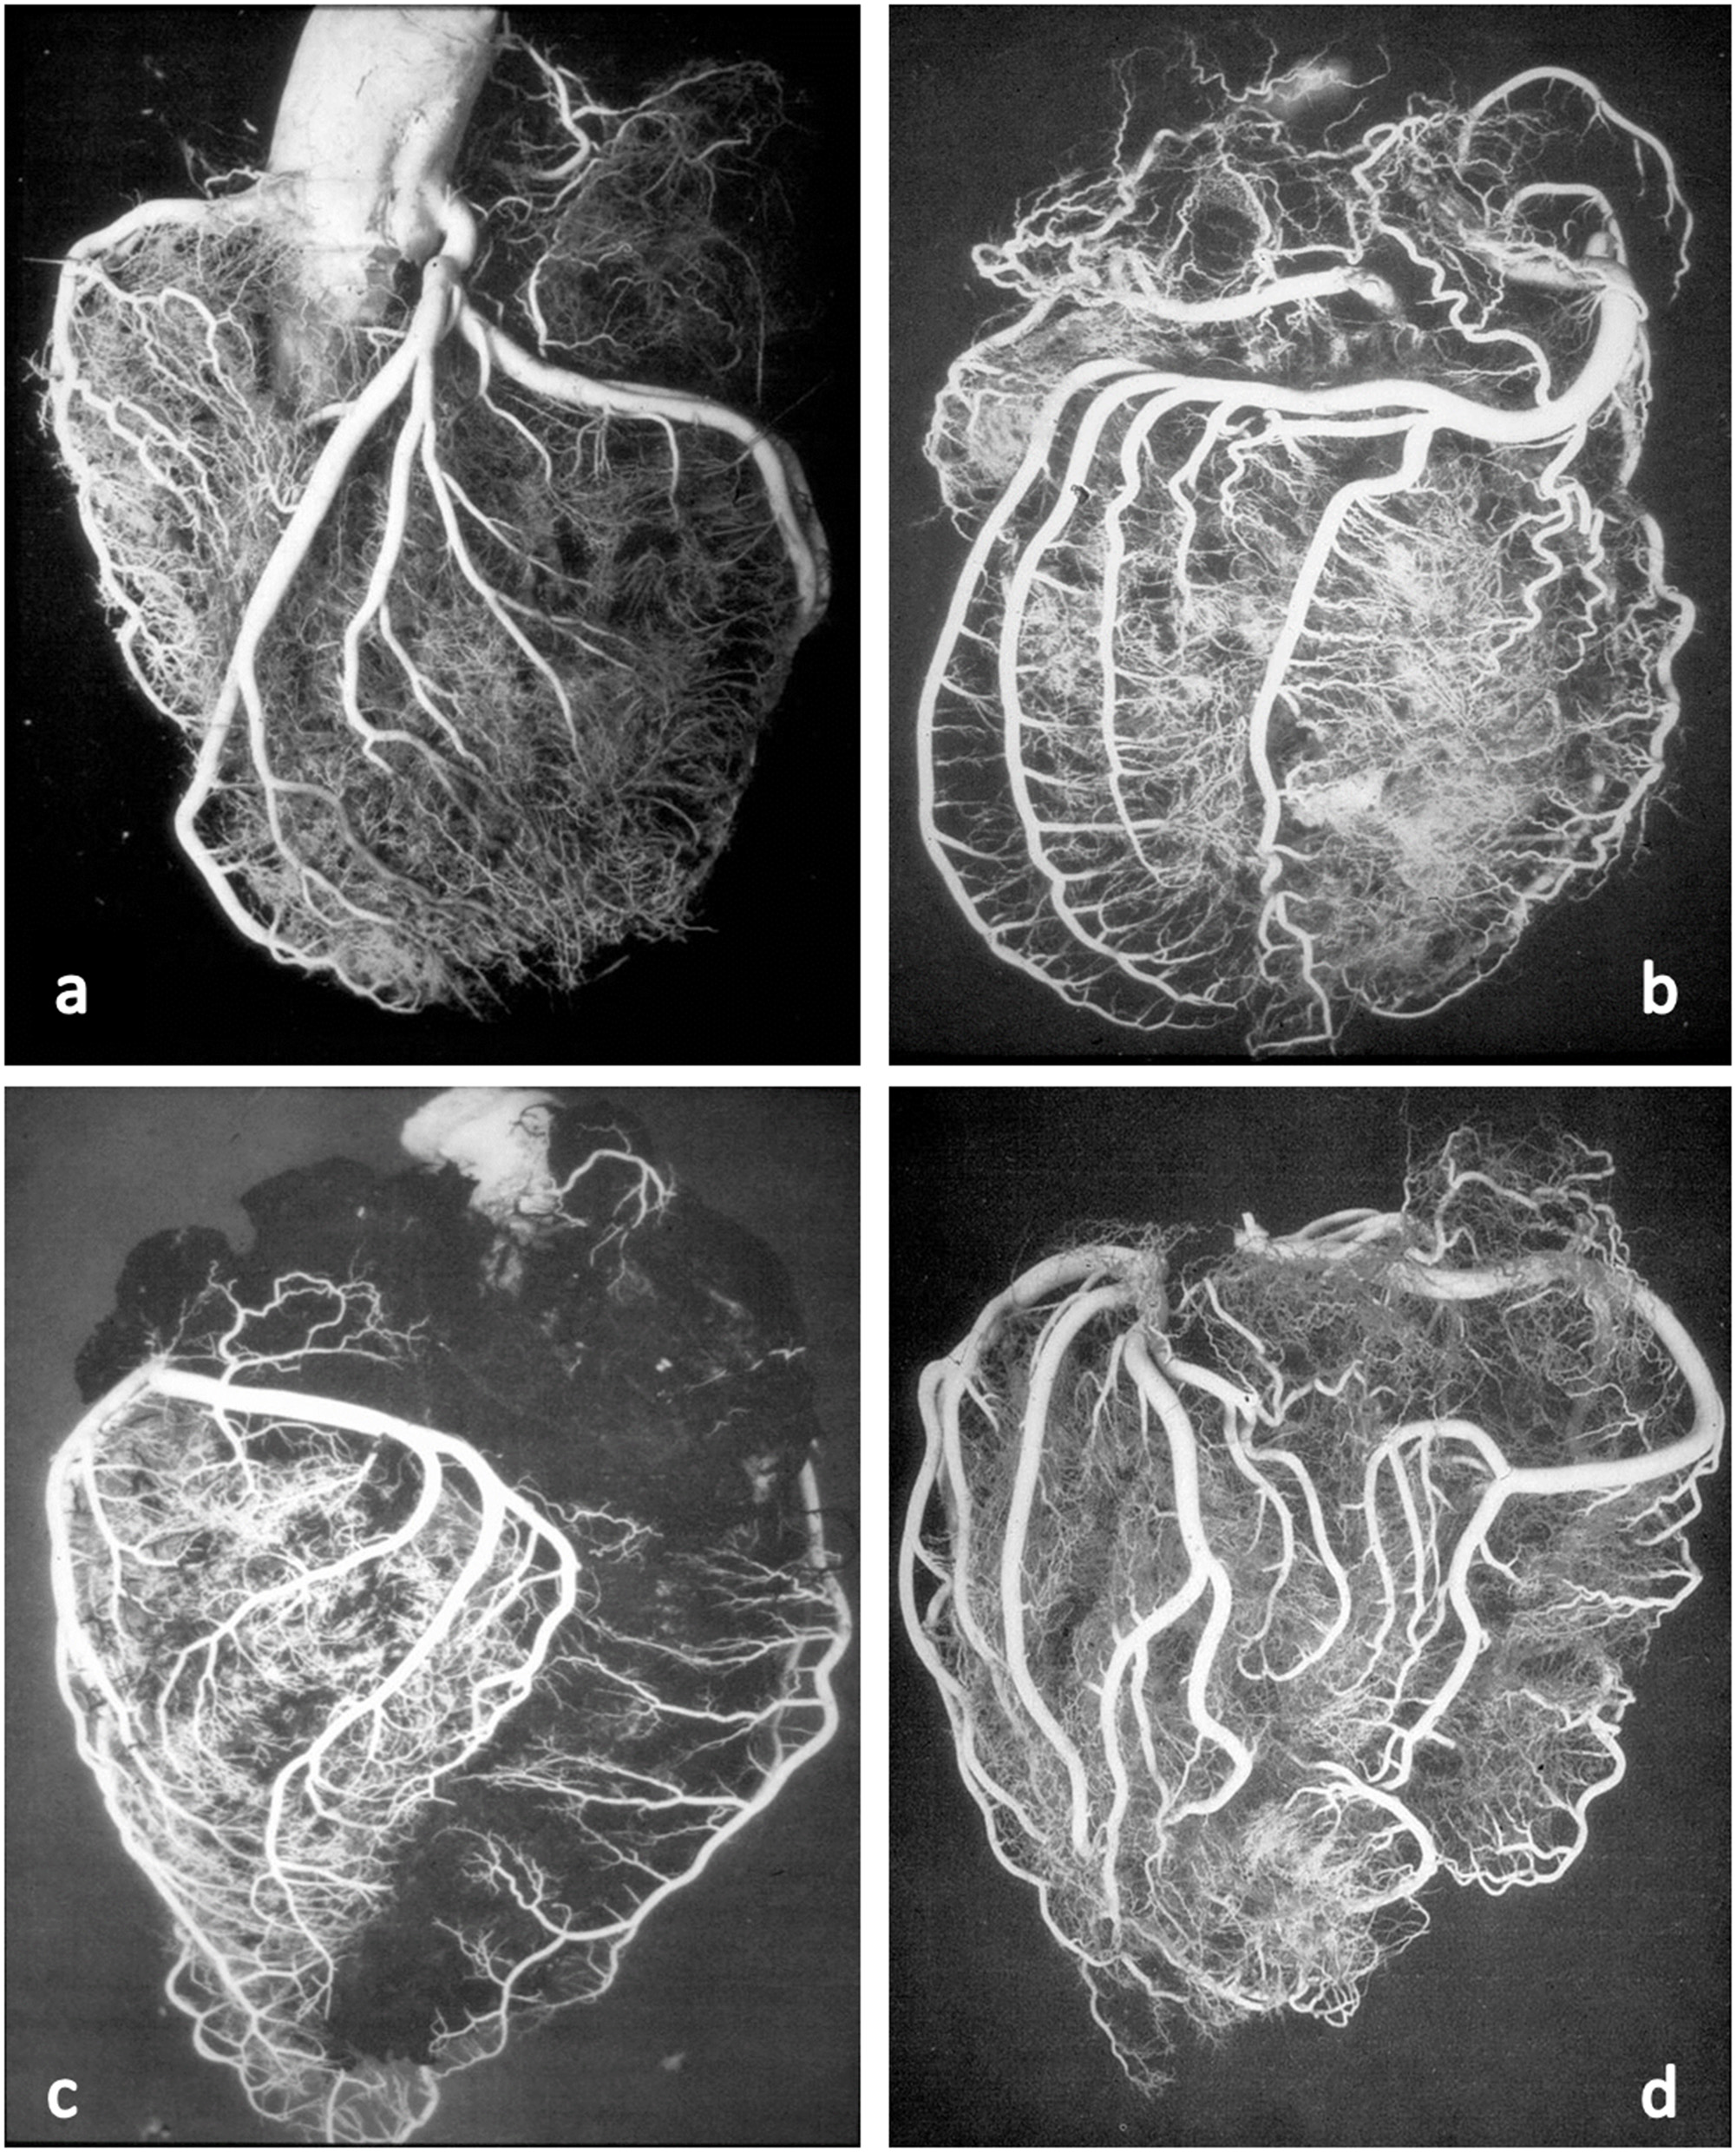

These anatomical patterns of the coronary arterial system were confirmed through postmortem injection and casts by Giorgio Baroldi in 1963 (Figure 2) (3). The plastic substances were “Geon Latex 576” and “Neoprene 842A.” These substances, which are fluid at room temperature, solidify at 40–50°C. They were injected into the aorta under pressure, ranging from 130 to 200 mmHg, maintained for a 5- to 10-min period.

Figure 2

Postmortem casts of coronary arteries. From Baroldi and Scomazzoni (3). (a) Left coronary artery anatomy, (b) dominant right pattern, (c) dominant left pattern, and (d) balanced pattern.